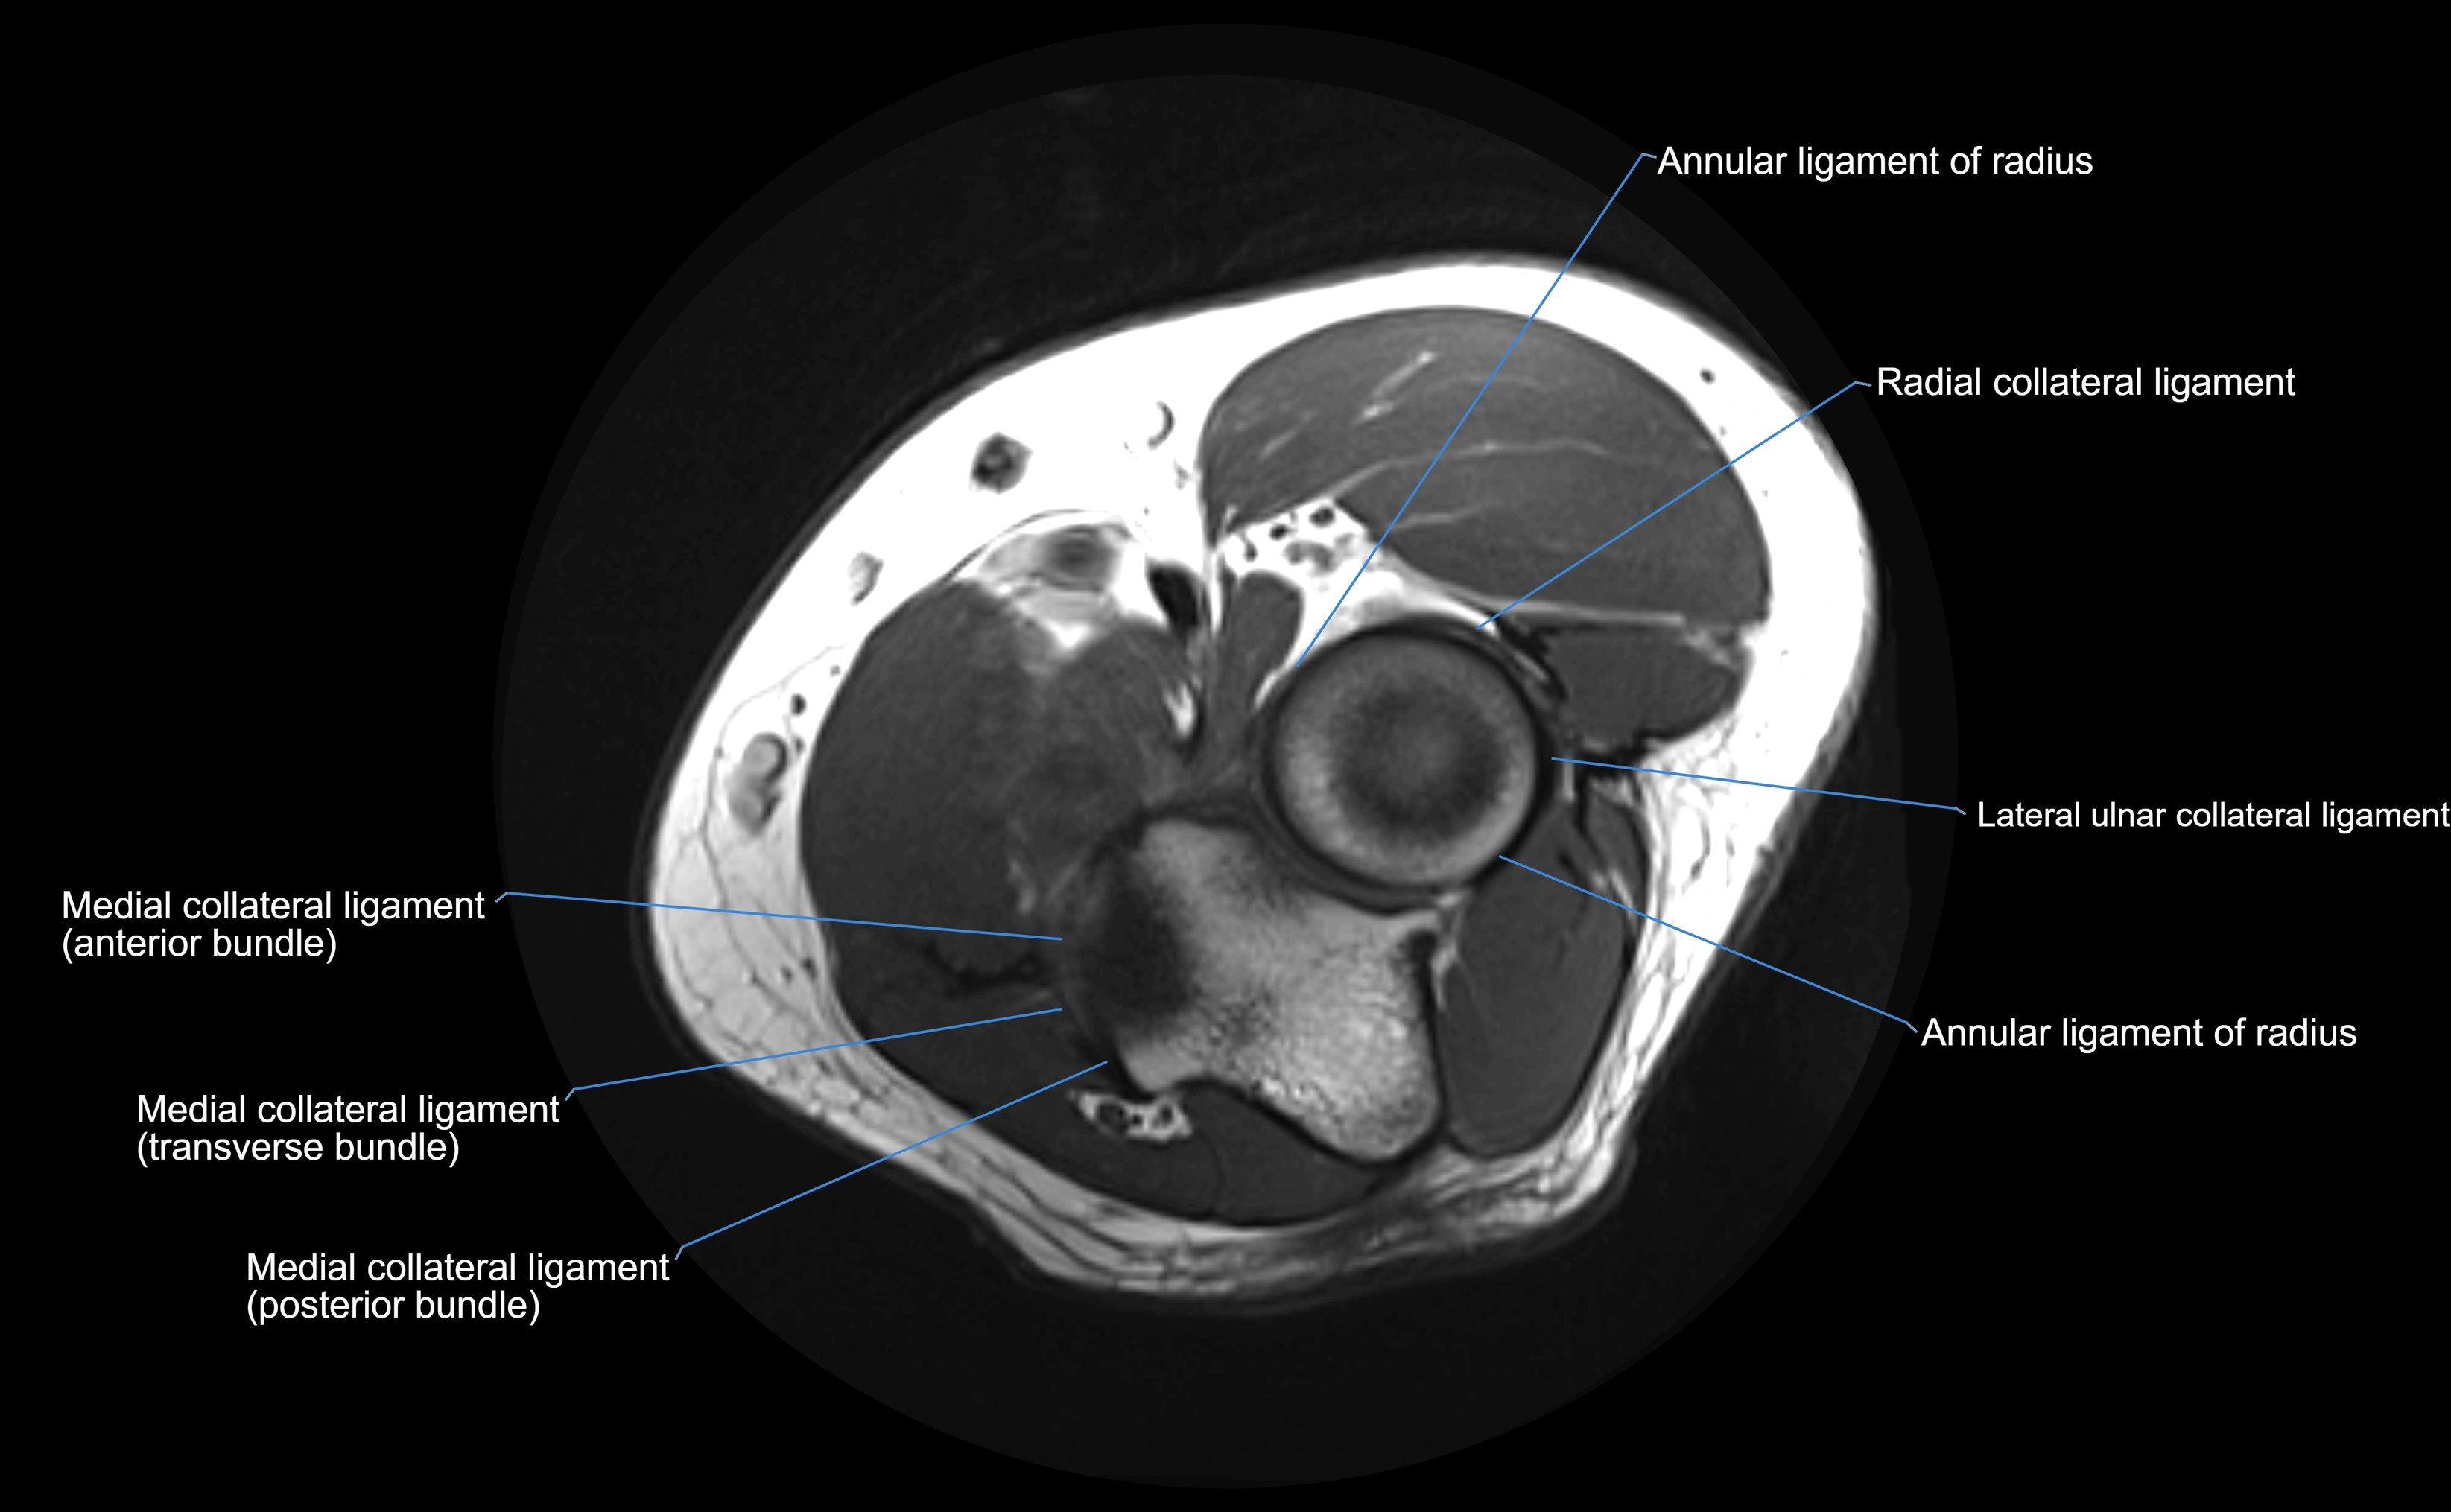

MRI Appearance

T1-weighted images:

• Ligament: low signal intensity (dark), appearing as a continuous band around the radial head.

• Adjacent fat and marrow: bright, creating contrast with the ligament.

• Thickening or disruption indicates injury or fibrosis.

• Joint capsule and synovium seen as thin low-signal lines contiguous with ligament margins.

T2-weighted images:

• Ligament: low signal (dark) with clear delineation from joint fluid.

• Fluid or edema: bright hyperintense, separating or surrounding the ligament in partial tears.

• Complete tear: discontinuity or non-visualization of ligament fibers, often with joint effusion.

STIR:

• Normal ligament: dark band encircling radial head.

• Pathology: bright hyperintense periligamentous signal suggesting edema, sprain, or partial tear.

Proton Density Fat-Saturated (PD FS):

• Normal: dark, well-defined band outlining the radial head.

• Partial tear: irregular or bright hyperintense signal within or adjacent to ligament fibers.

• Joint effusion and reactive synovitis appear bright and are well visualized.

MRI Arthrogram Appearance

• Contrast outlines the proximal radioulnar joint and radial head recess.

• Normal ligament appears as a dark ring surrounding the radial head, containing the injected contrast within the joint cavity.

• Partial tear: contrast extends along the ligament or beneath its fibers.

• Complete tear or subluxation: contrast extravasates around the radial head or ulna, indicating discontinuity.

• Detects capsular defects, instability, or synovial invagination with high sensitivity.

MRI images

image